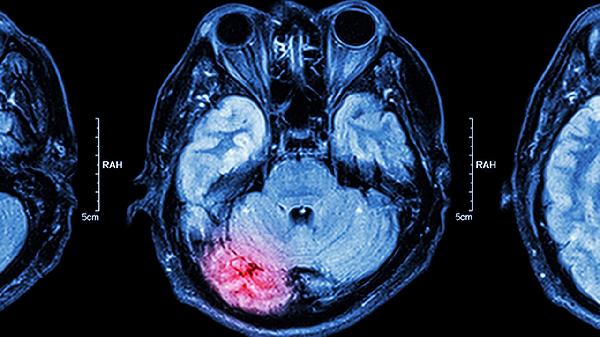

脑穿刺是否属于大手术需根据具体操作目的和范围判断。多数情况下脑穿刺属于微创操作,但涉及深部组织或复杂病变时可能归类为大手术。

当穿刺涉及脑实质深部病变、血管畸形或肿瘤切除时,操作复杂性和风险显著增加。这类情况需全身麻醉,可能使用立体定向导航等精密设备,手术时间超过2小时,术后需重症监护。并发症可能包括出血、癫痫或神经功能缺损,此时符合大手术的临床定义。例如脑脓肿穿刺引流或深部电极植入均属此类。